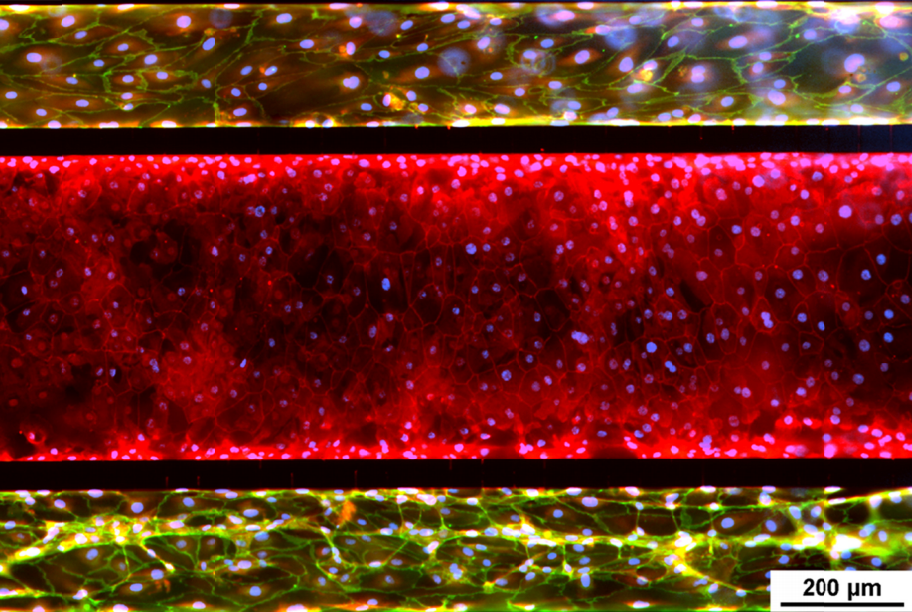

Modèle de poumon d'interface air-liquide SynALI